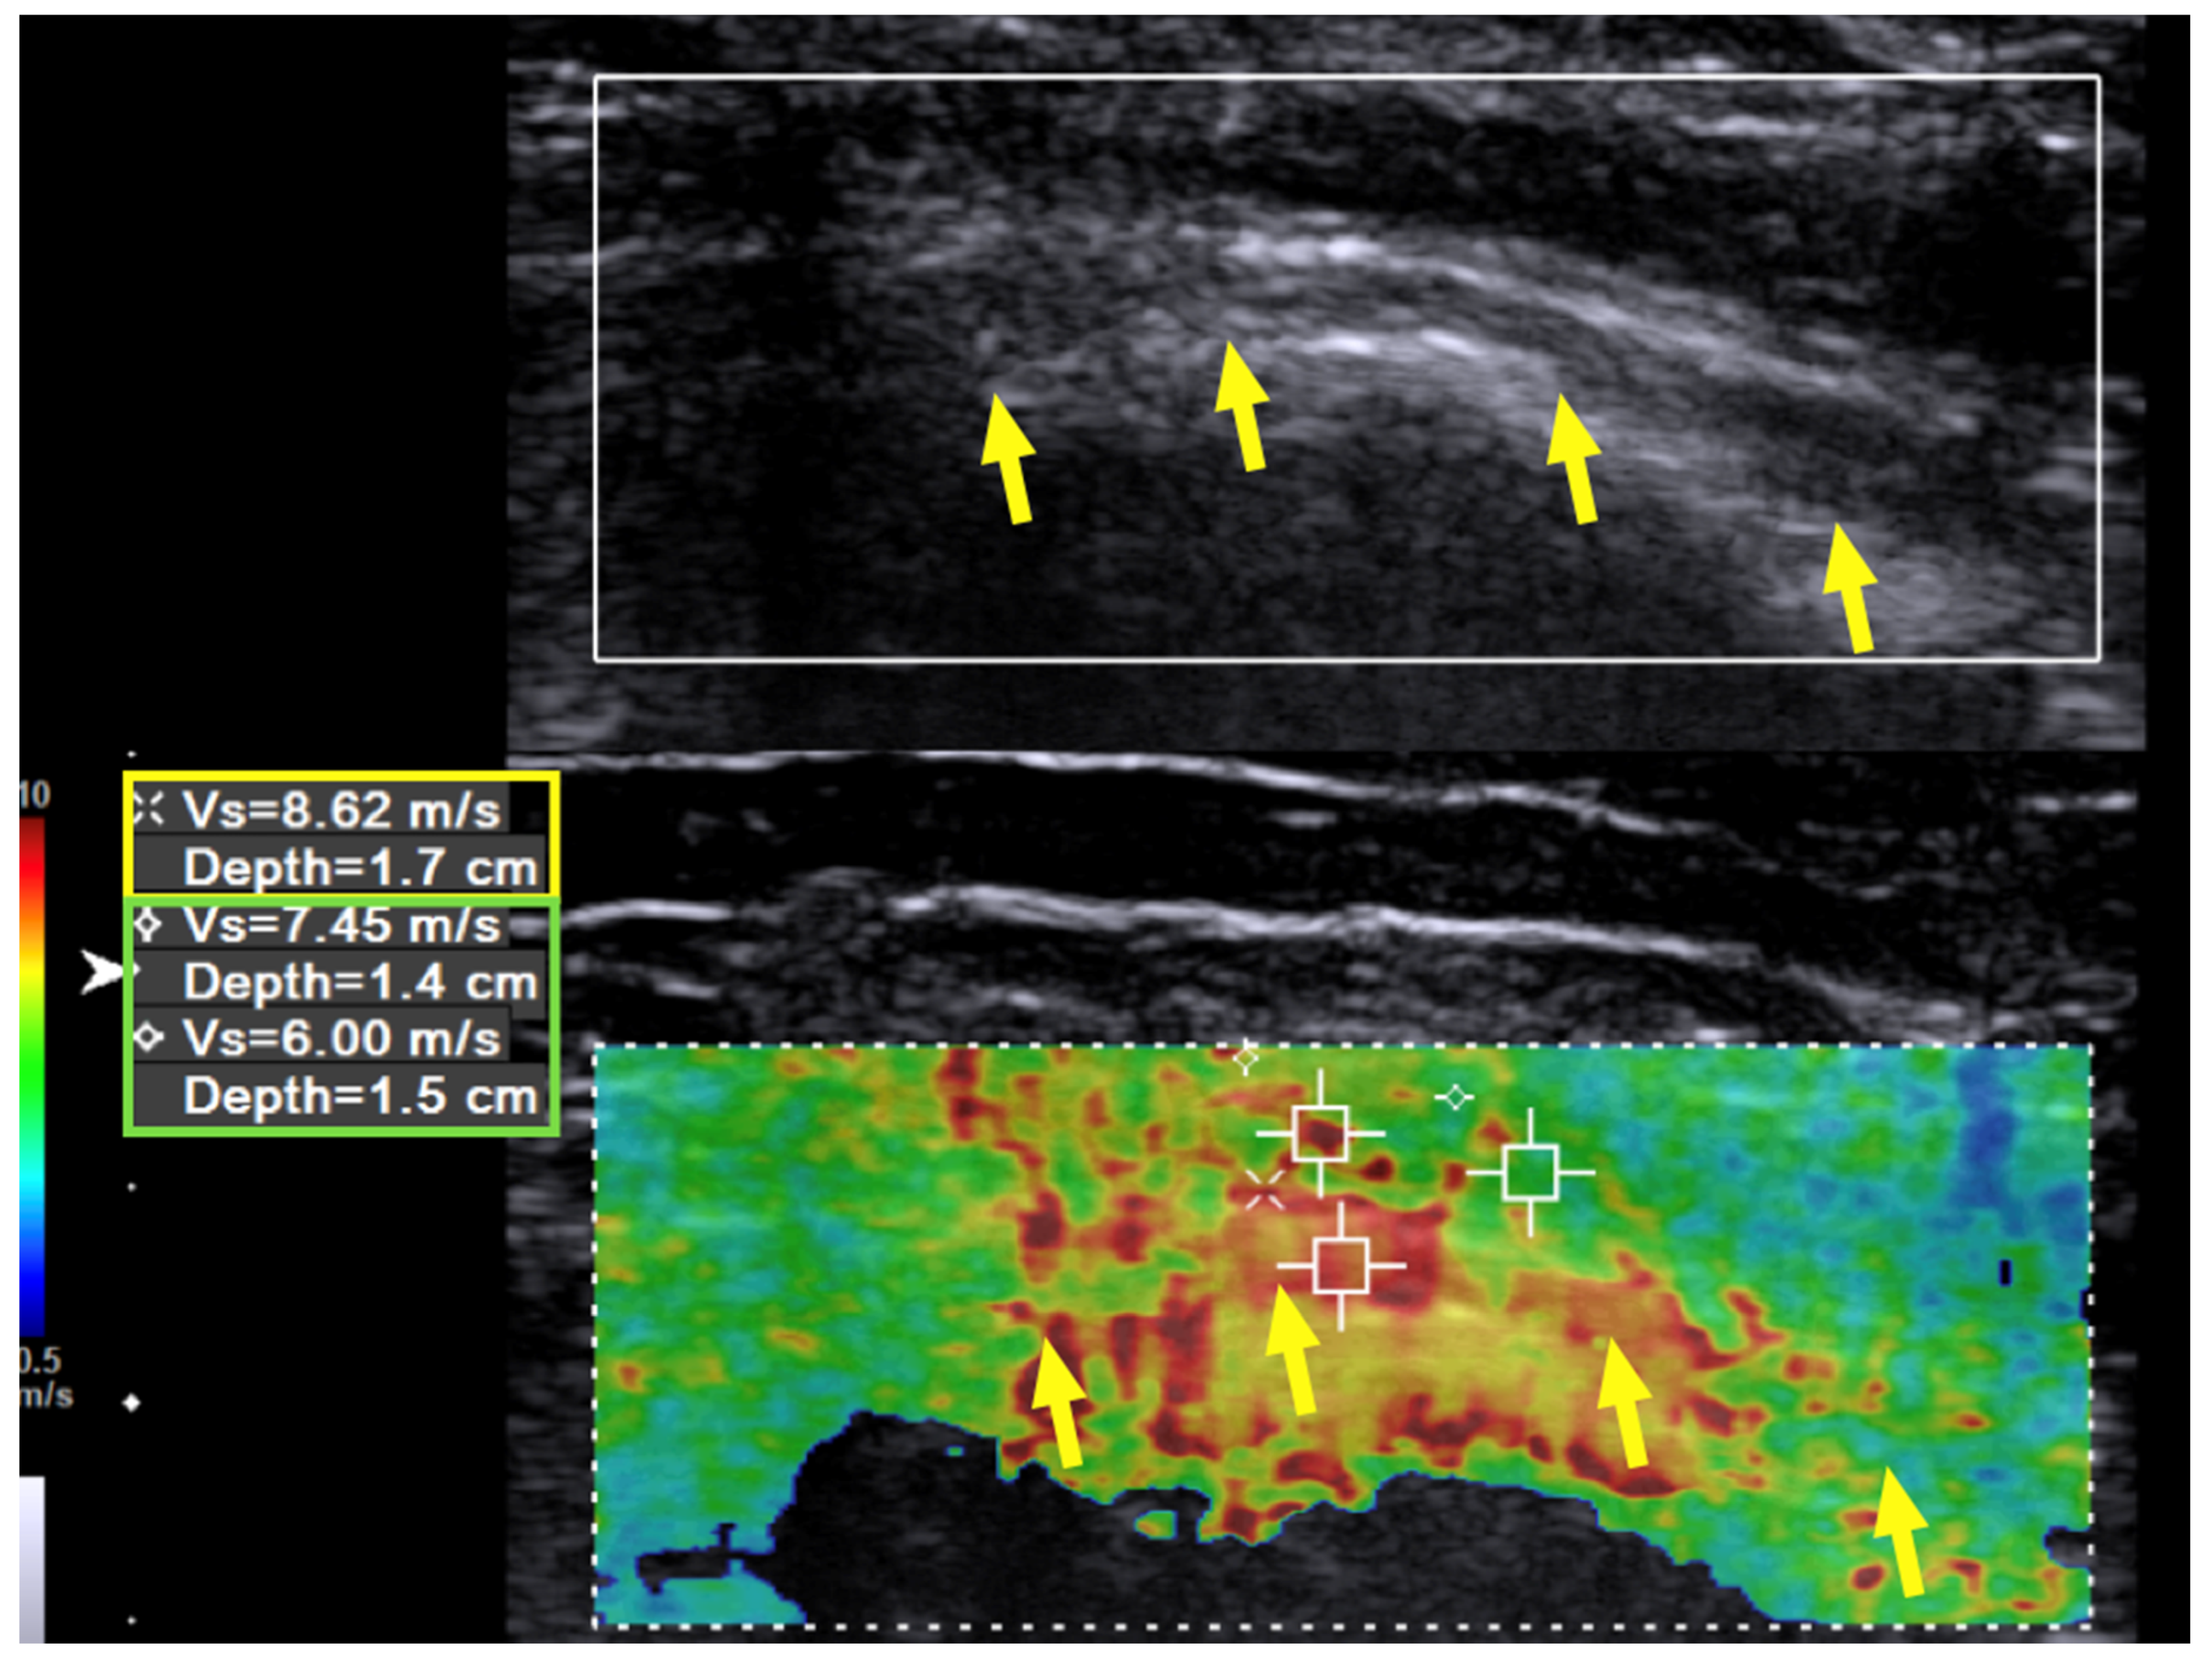

Immediately after the hydrodissection, the SWV was decreased temporarily due to the artifact of the injectate that infiltrated the soft tissue. The neuropathic pain was decreased from a VAS score of 8 to 2, and the patient experienced a sensation of local fullness. There was no muscle-power change immediately after the hydrodissection. When followed up two months after the last hydrodissection, the neuropathic pain had decreased from a VAS score of 8 to 3 (out of 10). The muscle power of the wrist extensors had considerably improved from 1 to 4 (on a scale of 0 to 5, with 5 being normal), and that of the finger extensors improved from 1 to 3. Neurodiagnostic studies revealed MUAPs over the supinator, ECRL, and EDC muscles, but MUAP remained absent over the EIP. US of the radial nerve still showed swelling and hypoechoic changes in the fascicles, as had been observed prior to treatment. However, the hardness of the surrounding tissue had decreased from 10.0 m/s to 7.45 m/s and in some areas even to 6 m/s (Figure 3, green box). The radial nerve hardness had decreased from 9.94 m/s to 8.62 m/s (Figure 3, yellow box).

Figure 3. Case 1: Shear wave velocity after hydrodissection. Shear wave velocity (SWV) investigation of the radial nerve (long axis) over the spiral groove after triple hydrodissection in a 31-year-old man with wrist drop following plate removal after humerus fracture osteosynthesis. After triple hydrodissection, the hardness of the scar (green box) and radial nerve (yellow box) over the spiral groove has decreased. Yellow arrow: radial nerve in longitudinal view.